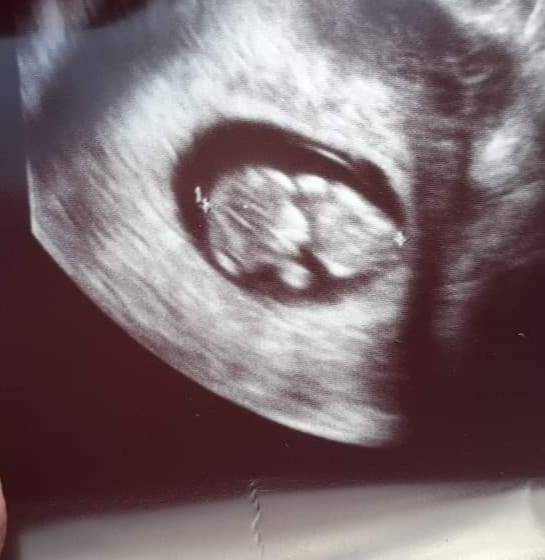

Czasem jak mam chwilę to coś się zobaczycie w necie i tak w pamięć zapada. No moja to już przedszkolak od tamtego roku. Więc zobaczymy jak przyjmie nowa rolę. Na chwilę obecną nie będę mówić bo wypapla wszystkim. Ale codziennie się pyta Mamo a w brzuszku jest malutka dzidzia😍

Serduszko jest dzidzia ma prawie 3cm...

Ale krwiak dalej jest nie zmniejszył się nawet o.milimert..